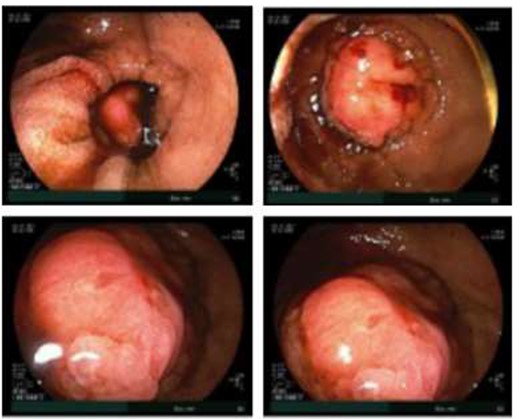

Given the patient’s anemia, melena and small bowel thickening, the patient was referred for upper and lower endoscopies, neither of which revealed the etiology of the patient’s symptoms. A pill endoscopy was also performed to evaluate the small intestine, though this was also unremarkable. The patient therefore underwent a double balloon enteroscopy, which was significant for a 3 cm small bowel mass located in the distal jejunum/proximal ileum (Fig. 2). The mass was biopsied and concerning for an adenocarcinoma. As a subsequent staging workup was negative for distant metastasis, the patient was taken for an exploratory laparotomy and small bowel resection. At the time of surgery, it was noted that the small bowel mass was located within an undiagnosed Meckel’s diverticulum (Fig. 3). The resected specimen was sent to pathology, which was significant for a moderately to poorly differentiated adenocarcinoma arising from a small bowel diverticulum, which was invading through the muscularis propria and into subserosal soft tissue with lymphovascular invasion (Fig. 4). The patient was therefore diagnosed with a Stage IIB (T4, N0) small bowel adenocarcinoma. After resection, the patient’s post-operative course was unremarkable, and he was discharged home on post-operative day 3. He was referred to medical oncology and is now receiving adjuvant capecitabine with oxaliplatin. As the patient’s resected specimen displayed negative margins, after completing the standard of care chemotherapy protocol, he will undergo active surveillance in accordance with the National Comprehensive Cancer Network guidelines.

Hematoxylin and eosin staining of the resected specimen showing a moderately to poorly differentiated adenocarcinoma.